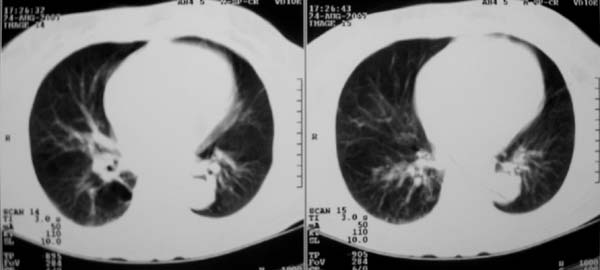

以下是引用zjzjr在2007-8-30 22:22:00的发言:[br]右上肺肺囊肿合并感染.右下肺肺大泡.左肺舌段感染.